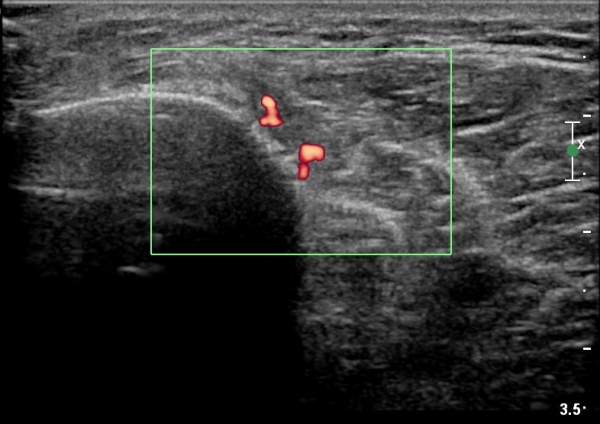

[¹«¸­] °æ°ñ ÇǷΰñÀý ÃÊÀ½ÆÄ¼Ò°ß(sonographic findings of stress fracture of tibia)

¿ìÃø ¹ß¸ñ°ú ¾Æ·§´Ù¸® ÅëÁõ(±â°£ 2ÁÖ)

±º´ë¿¡ ÀÔ´ëÇÏ¿© ÈÆ·ÃÀ» ¹ÞÀº º´·ÂÀÌ Àִ ȯÀÚ´Â ¾à 2ÁÖ ÀüºÎÅÍ ¹ß¸ñ ºÎÀ§ÀÇ ÅëÁõÀÌ ÀÖ´ø Áß

ÃÖ±Ù¿¡´Â ¹ß¸ñ À§ ¾Æ·§´Ù¸®¿¡ ÅëÁõÀÌ ¹ß»ýÇÏ°í ½ÉÇÏ°Ô °ÉÀ¸¸é ½ÉÇØÁö´Â ¾ç»óÀÓ

¾Æ·§´Ù¸® Áß°£ ºÎÀ§¿¡ °æ¹ÌÇÑ ¿¬ºÎÁ¶Á÷ ºÎÁ¾ÀÌ °üÂûµÇ°í ¾à°£ÀÇ ±¹¼ÒÀû ¾ÐÅëÀ» º¸ÀÓ.

ÃÊÀ½ÆÄ °Ë»ç